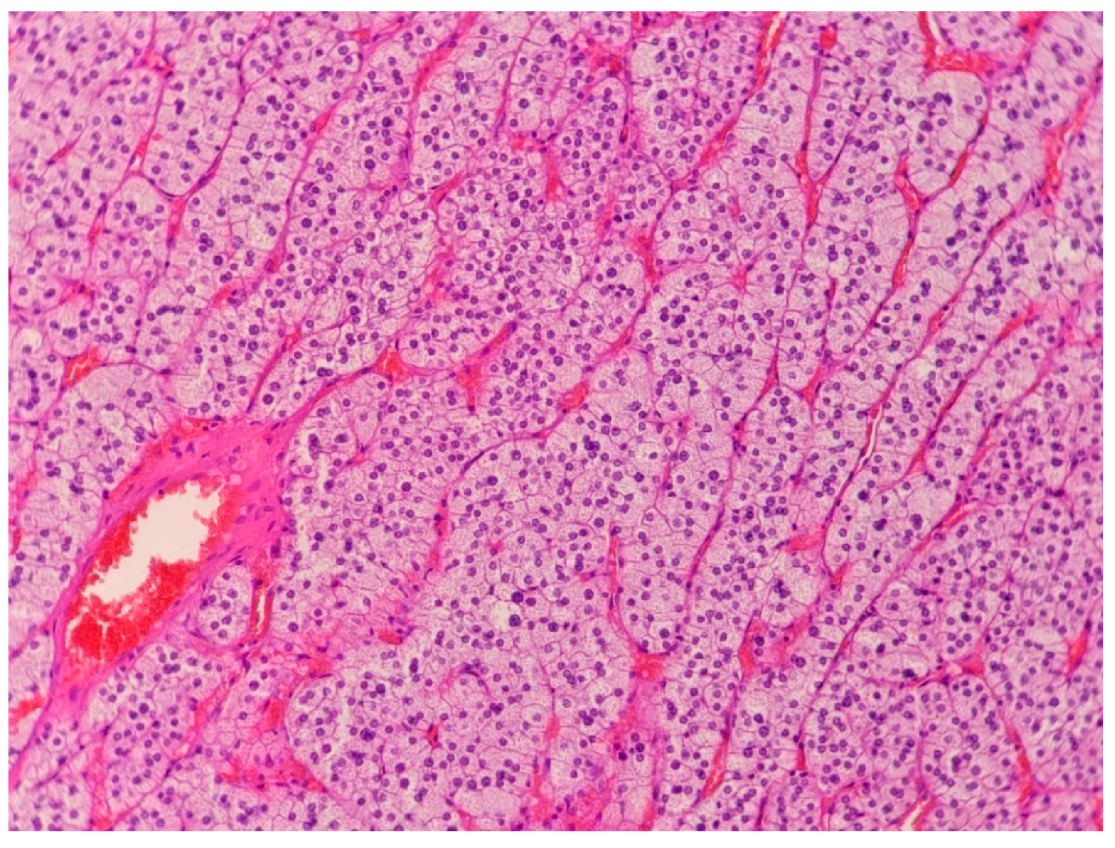

2.1. Case 1